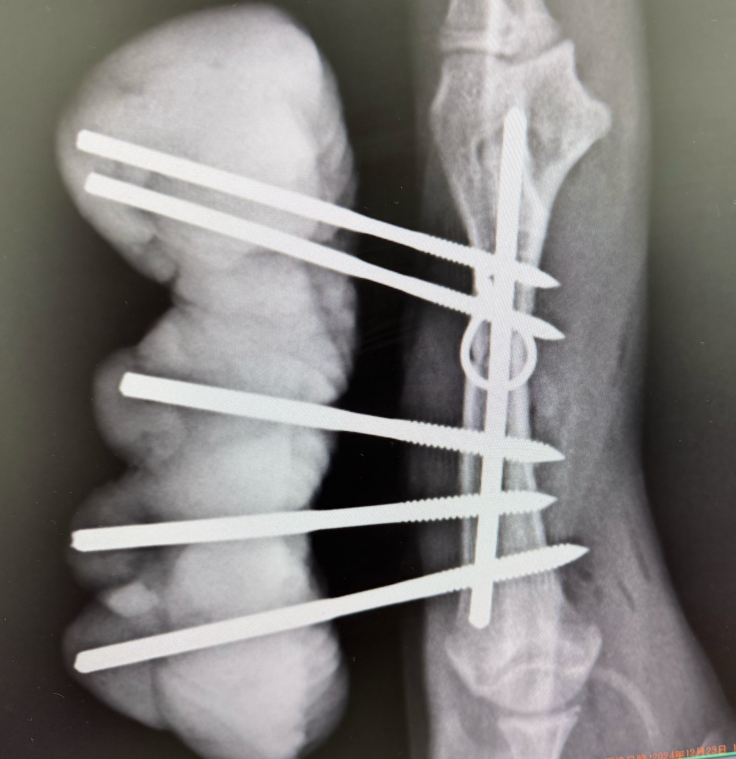

全身数カ所(少なくとも4.5箇所)骨折しています。

23日に一番骨折が酷かった前足の手術をしました。

創外固定手術をしました。